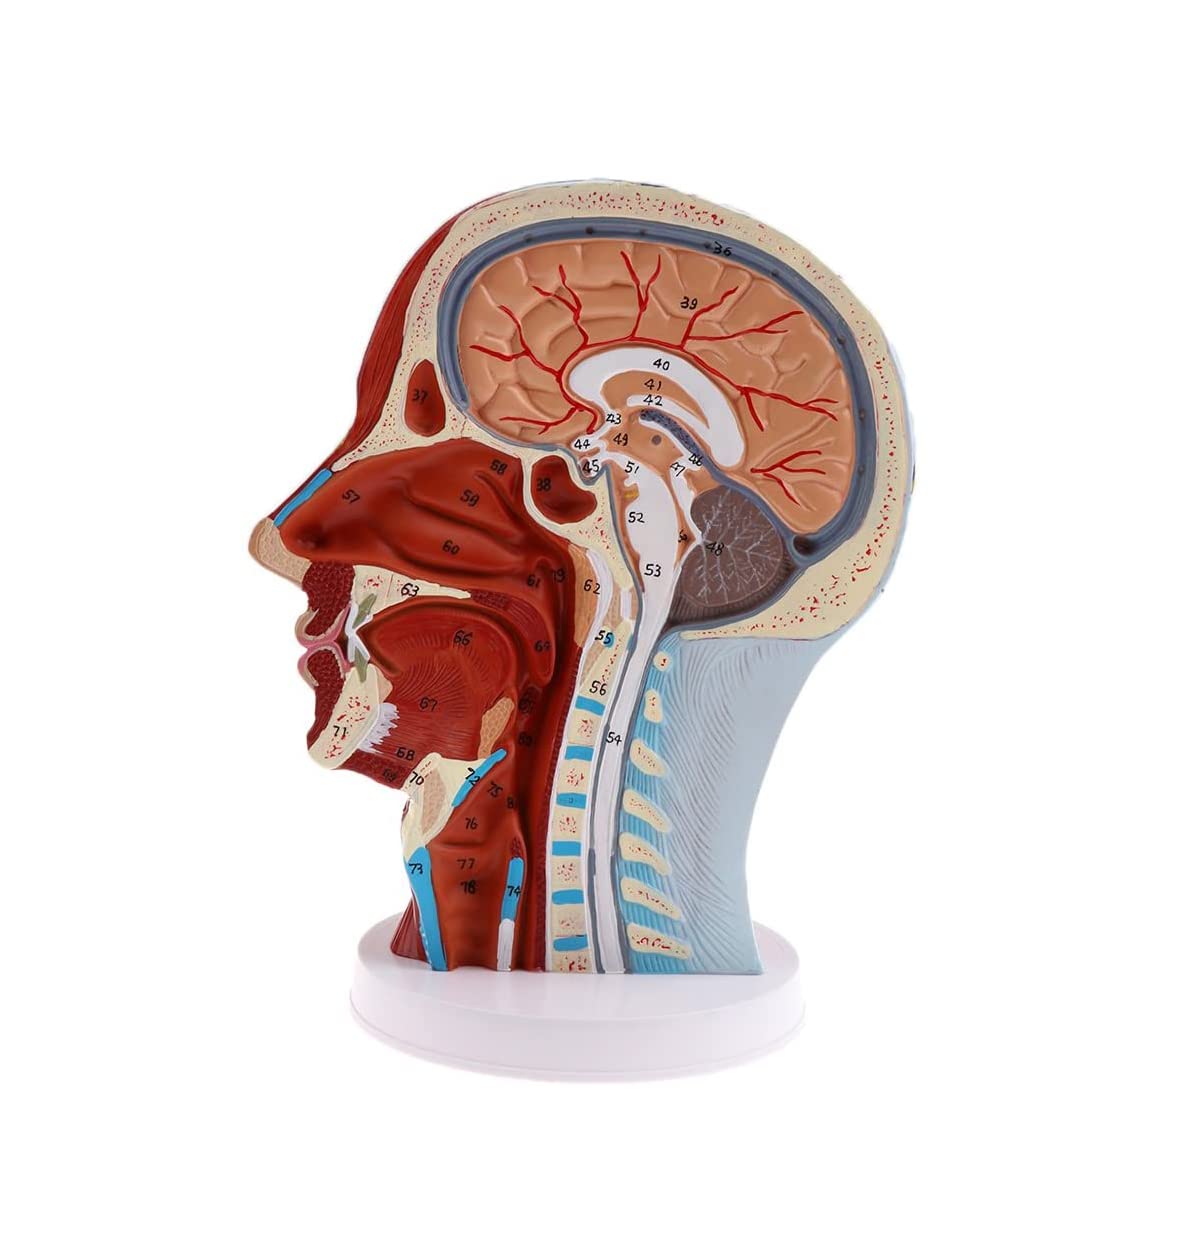

Description:A natural lifesize superficial neurovascular muscle modelMaterial: PVC, PC programmed advanced paintingHighly accurate 3D printing and spatial structureShows details of the human right head and neck and median sagittal plane, including exposed superficial muscles of face, superficial blood vessels, nerves, and parotids of face and scalp, the inner structure of the upper respiratory tract and the sagittal section of cervical spineSuitable for teaching, display, presentation and demonstration in hospital and aesthetic field.Specification:Size: 27 x 21 x 21.5 cm/ 10.6 x 8.3 x 8.5 inchPackage Includes:1 Piece brain model